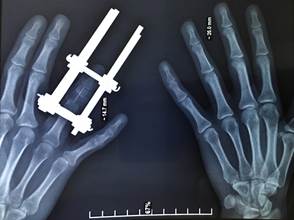

Пациентке была проведена рентгенография правой кисти, которая позволила детально проанализировать размеры средней фаланги четвёртого пальца правой кисти. Это исследование было выполнено для максимально точного подбора параметров имплантата, включая его диаметр и длину, что является важным этапом подготовки к предстоящему медицинскому вмешательству. Полученные данные обеспечили высокую точность и эффективность лечения, минимизировали возможные риски и гарантировали оптимальные результаты для пациентки (рис. 2).

Рис. 2. Рентгенограмма здоровой правой кисти

Источник: фото из архива автора.

Неотъемлемой частью процесса является проведение математического моделирования реконструируемой конечности с целью создания 3D-модели структур, необходимых для восстановления. На основании данных, полученных при измерении правой здоровой кисти пациентки, был разработан и изготовлен индивидуальный наноструктурный имплантат нужных размеров для замещения костного дефекта. Также были подготовлены имплантаты для реконструкции проксимального межфалангового сустава.

Операционный доступ осуществлялся через тыльную поверхность средней фаланги. Имплантат вводился в рану, замещая дефект, и фиксировался к дистальному отломку кости с использованием спицы. В проксимальный конец имплантата закреплялась дистальная часть протеза межфалангового сустава с применением костного цемента, при этом проксимальная часть протеза фиксировалась в проксимальный отломок кости без особенностей (рис. 3).

![]() |

Рис. 3. Рентгенологическая картина после оперативного вмешательства (имплантированная и фиксированная конструкция)